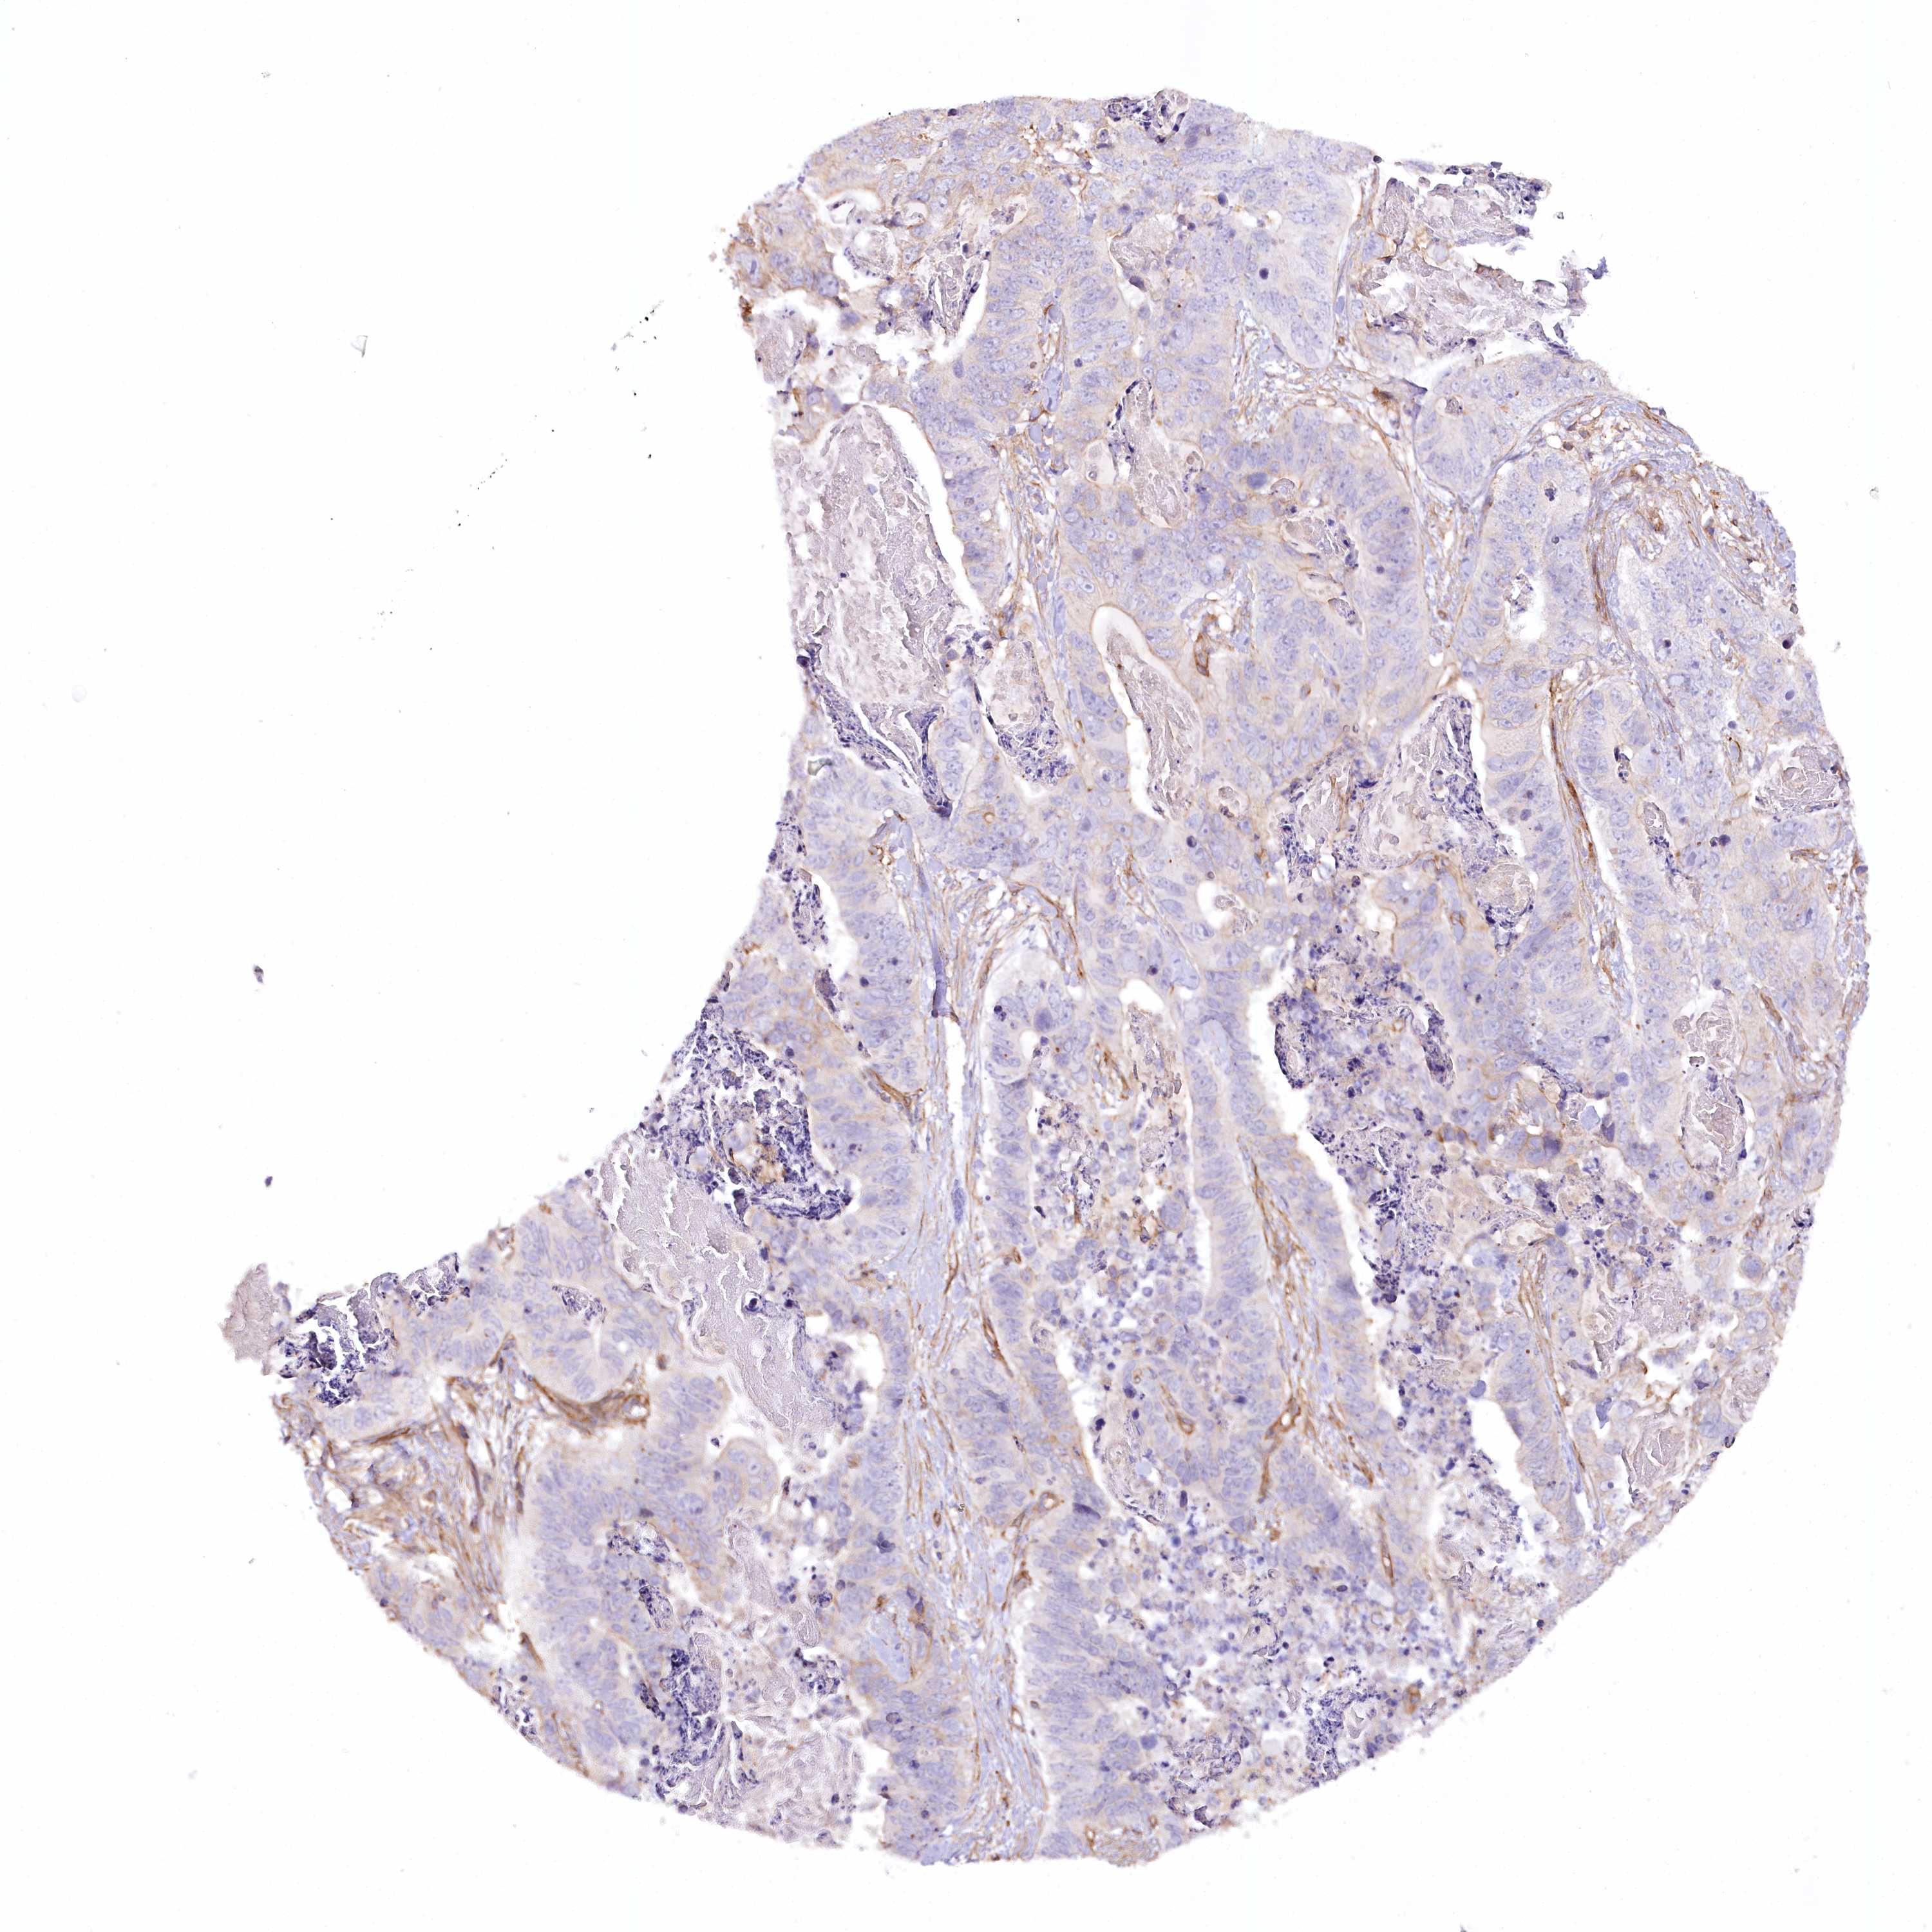

STOMACH CANCER - Protein expressioni

A mouse-over function shows sample information and annotation data. Click on an image to view it in a full screen mode. Samples can be filtered based on level of antibody staining by selecting one or several of the following categories: high, medium, low and not detected. The assay and annotation is described here.

Note that samples used for immunohistochemistry by the Human Protein Atlas do not correspond to samples in the TCGA dataset.

Antibody stainingi

Antibody staining in the annotated cell types in the current human tissue is reported as not detected, low, medium, or high, based on conventional immunohistochemistry profiling in selected tissues. This score is based on the combination of the staining intensity and fraction of stained cells.

Each image is clickable and will lead to virtual microscopy that enables deeper exploration of all samples and also displays staining intensity scores, fraction scores and subcellular localization as well as patient and tissue information for each sample.

Antibody HPA030665

Antibody HPA068563

Antibody CAB037231

Staining

High

Medium

Low

Not detected

Intensity

Strong

Moderate

Weak

Negative

Quantity

>75%

75%-25%

<25%

None

Location

Nuclear

Cytoplasmic/membranous

Cytoplasmic/membranous,nuclear

Adenocarcinoma, NOS